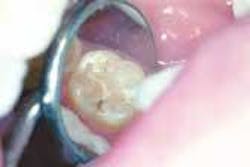

Because the failure rate among sealants is so high, we meticulously examine each sealant our patients have. The examination includes placing a caries-detection dye on the sealants using high resolution video-imaging. If a sealant is leaking, good magnification will show the tint of the dye under the sealant. A failed sealant is then easily removed, utilizing the parallel water stream technique. The operative field is flooded with water, while air abrasion is simultaneously used to selectively remove the sealant.